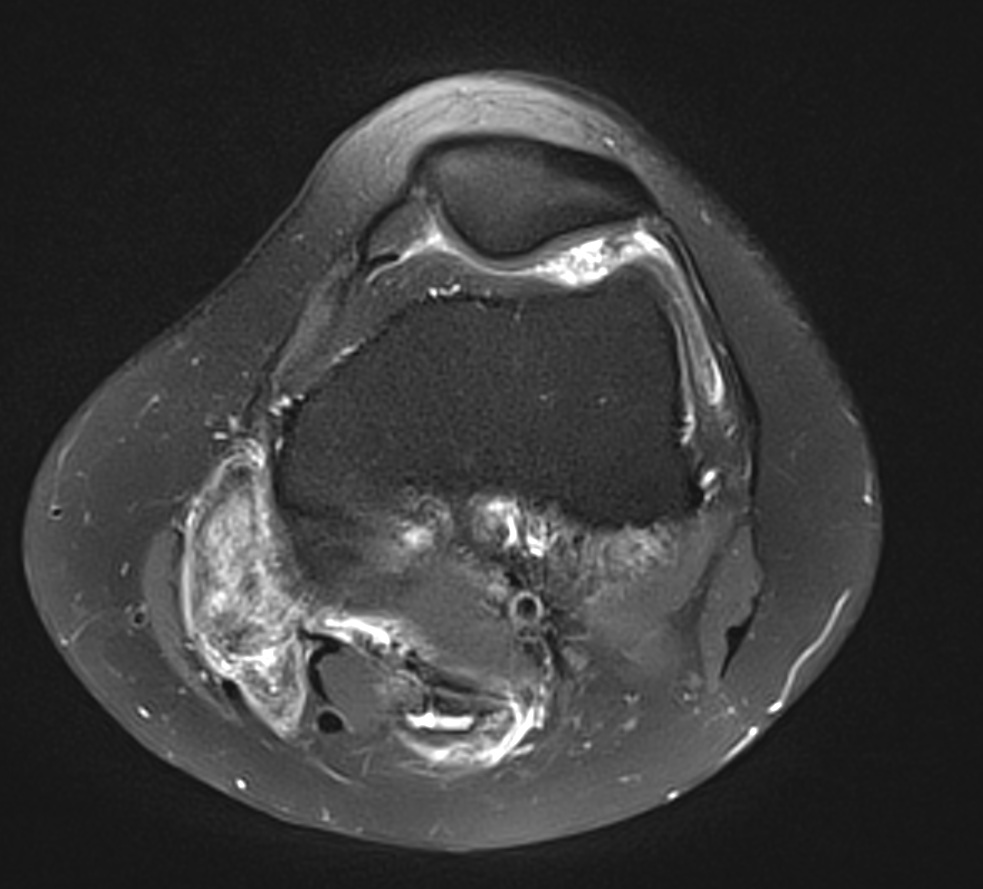

Synovite villo-nodulaire du genou

Synovite villo-nodulaire du genou 2